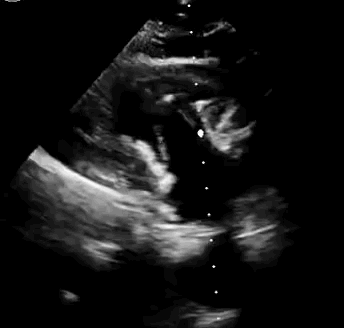

本次臨床前研究經(jīng)右側(cè)頸靜脈置入LuX-Valve Plus輸送系統(tǒng)可調(diào)彎鞘管,在DSA及超聲引導(dǎo)下將人工三尖瓣瓣膜植入到原有三尖瓣位置,利用獨特的錨定技術(shù)將人工瓣膜支架可靠固定在預(yù)定的位置。